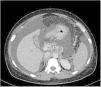

Axial abdominal CT image with intravenous contrast enhancement. Indirect signs of portal hypertension can be seen (collateral circulation with perisplenic and perigastric varices, mild splenomegaly, important hydropic decompensation, with abundant ascites in all compartments), with a homogeneous liver parenchyma showing no signs of advanced chronic liver disease or focal lesions.